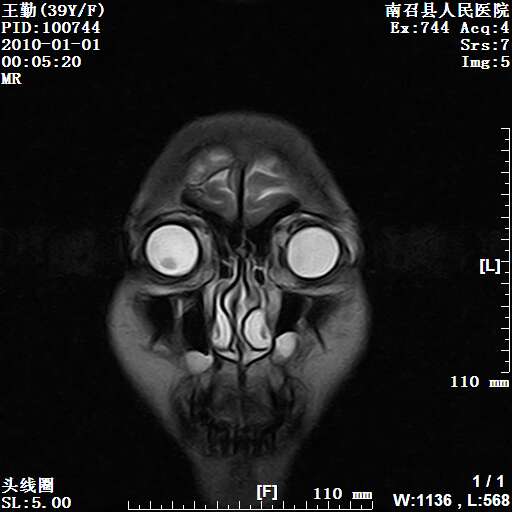

以下是引用随光逐影在2010-1-22 9:03:00的发言:[br]考虑左侧中颅窝(蝶骨翼区)脑膜瘤侵犯蝶骨翼并突入左侧眼眶。

以下是引用水过无痕在2010-1-22 14:55:00的发言:[br]一、定位:颅外占位;二、定性:恶性可能性大;三、组织来源:来源于左侧眼外直肌或其他部位;考虑为:横纹肌肉瘤>转移瘤>脑膜瘤.